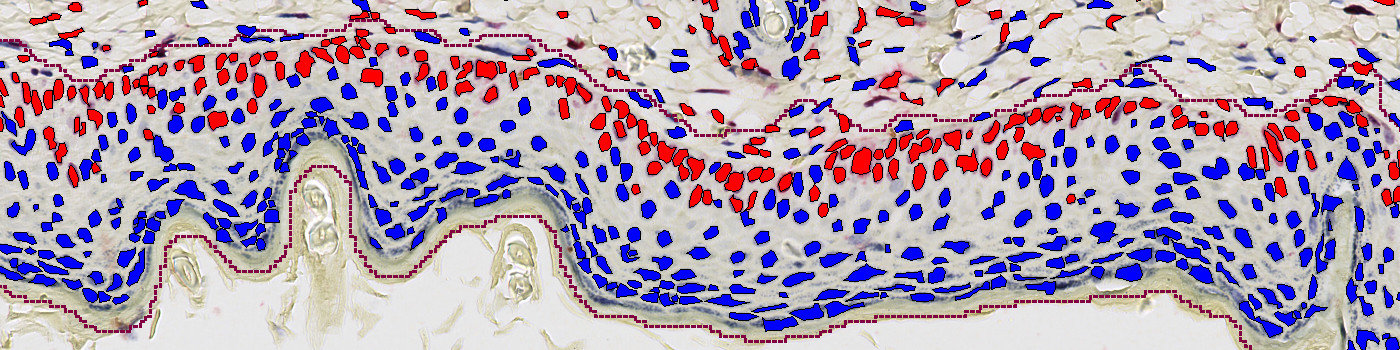

The Ki-67 protein is expressed in the nucleus and is a marker for cell proliferation. Increased number of Ki-67 positive cells in epidermis indicates increased epidermal hyperplasia, a characteristic which is associated with various inflammatory skin diseases as atopic dermatitis and psoriasis, see [1].

This protocol can be used to assess the number of Ki-67 positive cells in epidermis. The protocol provides the number and area of Ki-67 positive cells within the epidermis region, as well as for the entire tissue section. Manual assessment of the outlined epidermis region can be necessary.

Step 4: Load the cell detection protocol “04 Ki67 Cell Detection”.

The first image processing step is a rough outline of tissue. This is performed to limit the subsequent quantitative analysis and to facilitate numbering of tissue samples in cases with multiple samples per slide. The next processing step involves a segmentation of epidermis, followed by an exclusion of hair cells. The length of epidermis is calculated using the skeletonize feature. The rough outline and final region of interest (ROI) is seen in FIGURE 1 and 2, respectively. The final processing step includes a detection and quantification of positive nuclei in each ROI.